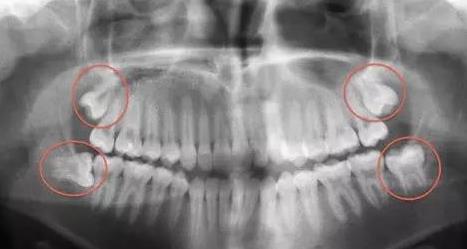

1、相似的青春片,不同的青春片~

牙醫眼裏的青春片——長這樣:

為(wei) 什麽(me) 把智齒的牙片,叫做青春片呢?

智齒,通常是在青春時期長出的,長出的時候姿勢妖嬈,千姿百態,朝氣蓬勃,但是卻經常做傻事(引起疼痛和炎症)就像是一個(ge) 孩子正值青春期,雖然叛逆,但是有著敢闖敢拚的勁兒(er) !